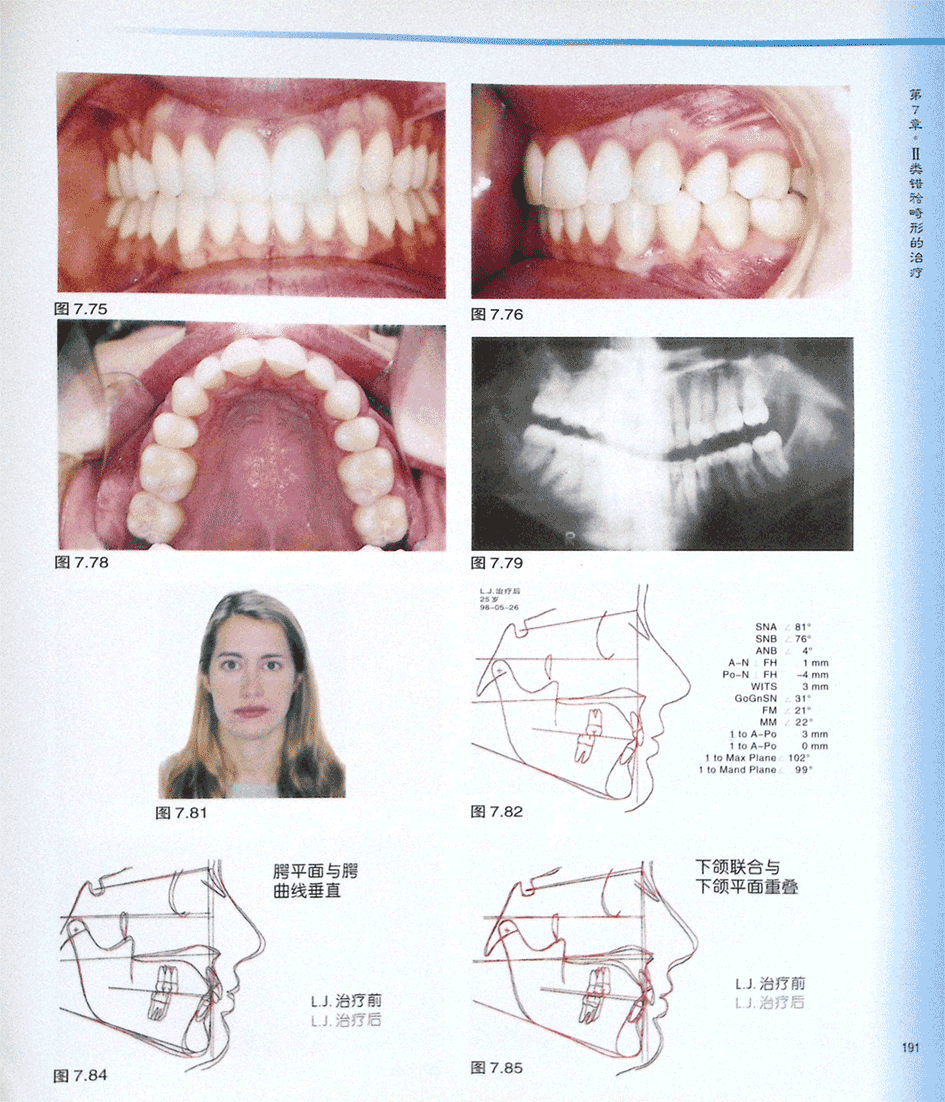

病例 成人Ⅱ类深覆牙合拔除上颌第一前磨牙和所有第三磨牙(二)